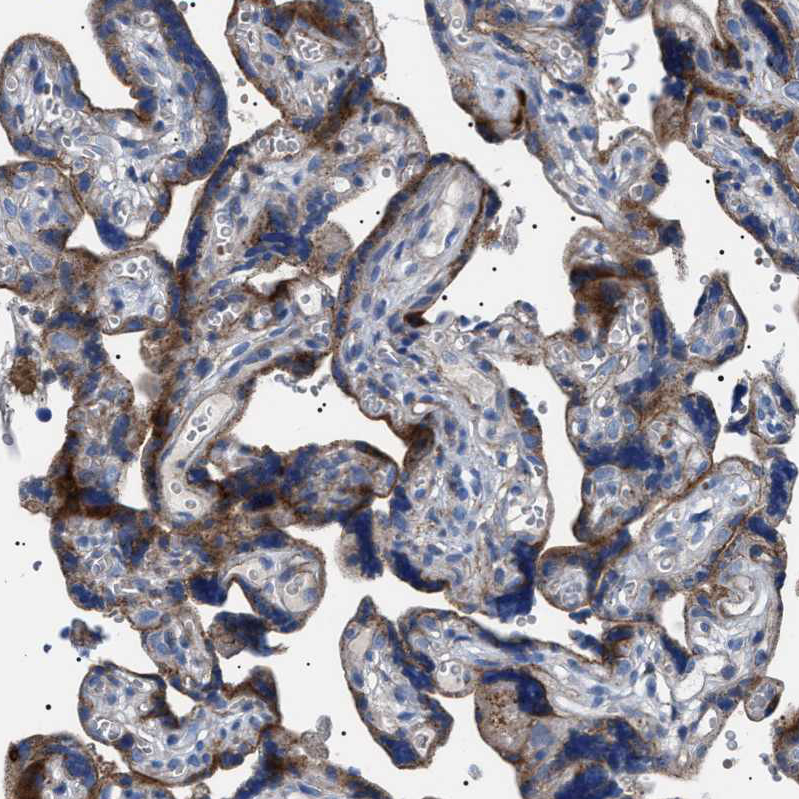

Immunohistochemical staining of human kidney shows strong granular cytoplasmic positivity in cells in tubules, while glomeruli are negative.